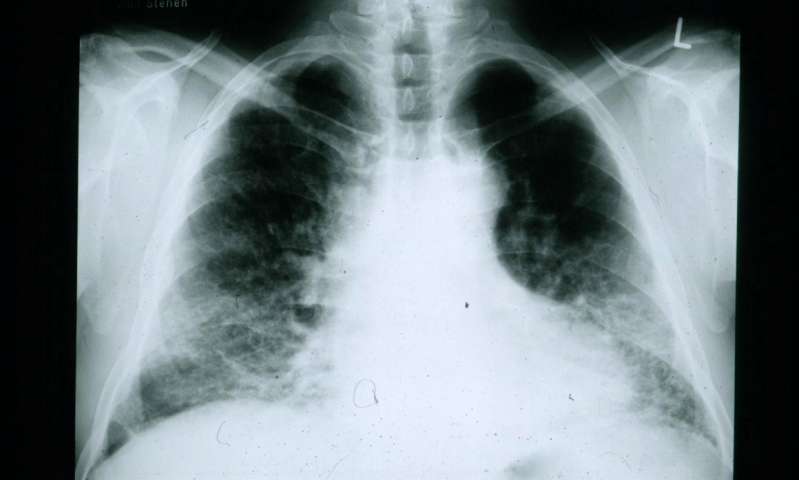

【检测肺癌新工具】肺癌依然是主要癌症杀手,但是一旦发现就已经为时已晚了。然而近期,研究人员发现有一天也许可以通过一个简单的鼻拭子,就可以快速使用 CT 扫描出肺癌。

目前,医生通过对长期吸烟者或其他高风险人群进行胸部扫描,一旦发现异常,一系列的检查,如活检都是必不可少的。因此,需要更加方便,简洁且安全有效的检测方法。